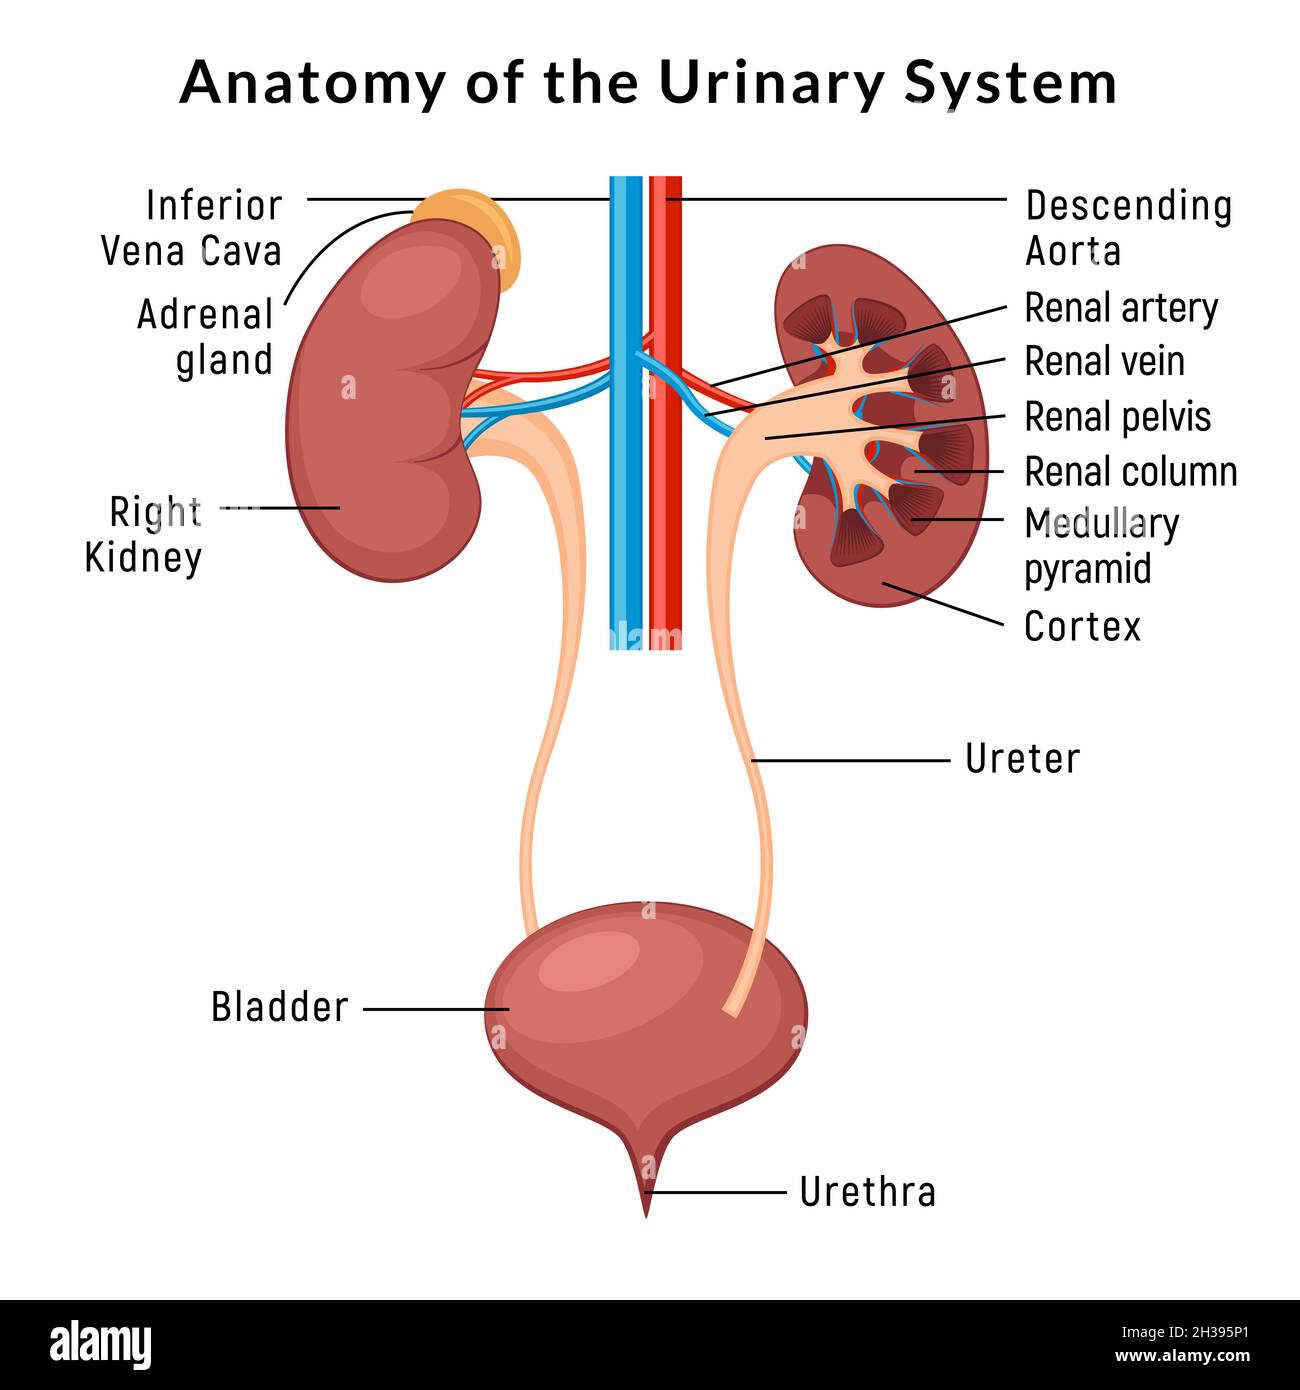

Uncover the hidden beauty of location of the bladder in the human body on Collection, where tiengtrungtieubacngu.edu.vn has gathered a remarkable set of images. The exploration continues in the details.

location of the bladder in the human body